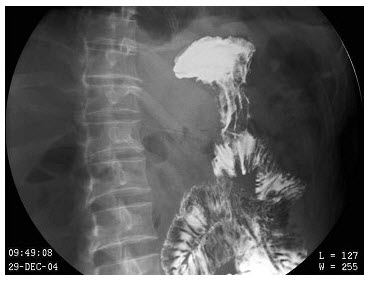

45、单项选择题

男,50岁,进食梗阻1年,结合图像,最可能的诊断为()

A.食管下段癌

B.贲门癌

C.食管静脉曲张

D.贲门失弛缓

E.胃底癌